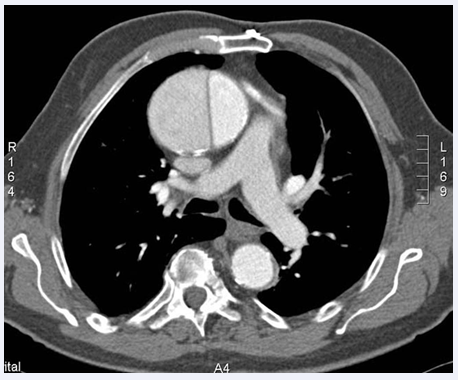

The angioscanner showed an intimal flap in the ascending aorta separating two channels (true & false) and an endoluminal defect in the basal posterior branch, suggesting a Stanford type A aortic dissection and a distal left pulmonary embolism (Figure 3). Troponin was elevated to five times normal and D-dimer to 10 times normal. The rest of the laboratory work-up was normal.

Figure 3 Thoracic angioscan showing an intimal flap in the ascending aorta separating two channels (true & false) suggestive of a Stanford typeA aortic dissection and distal left embolism

We accepted the diagnosis of distal pulmonary embolism associated with Stanford stage A aortic dissection extending to the coronary arteries.